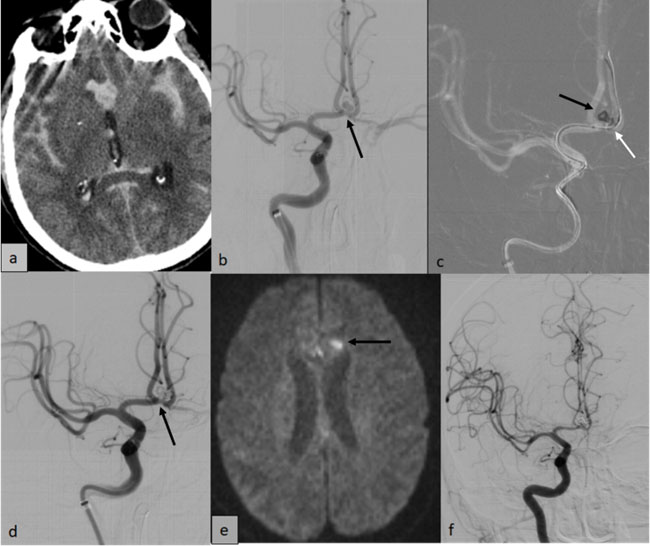

A 57-year-old woman presented with sudden severe headache followed by transient loss of consciousness. On arrival, she was drowsy but maintained a GCS of 15 with no focal deficits. CT brain revealed diffuse thick subarachnoid hemorrhage (SAH) (modified Fisher grade IV) with a small right paramedian frontal hematoma and intraventricular extension of bleed (Fig. 2a). CT angiography showed a small saccular anterior communicating artery (ACom) aneurysm.

She underwent DSA and endovascular coiling on the same day (Day 1 of ictus). The procedure was done under general anesthesia through right common femoral arterial access. DSA showed a bilobed, narrow-necked (~5 × 2.5 mm) aneurysm at the left A2–ACom junction (Fig. 2b). Balloon-assisted coiling was performed using two detachable coils (Target 3mm x 6cm, 2mm x 2.5cm, Stryker), achieving near-complete occlusion with preserved distal flow (Fig. 2c, d).

She was extubated the same night and monitored in the ICU. On Day 5, she developed sudden quadriparesis (power 1/5). MRI revealed multifocal acute lacunar infarcts (Fig. 2e). Urgent DSA demonstrated mild diffuse vasospasm (Fig. 2f). Intra-arterial Nimodipine (1.5 mg) and Milrinone (2.5 mg) were administered bilaterally, followed by IV Milrinone infusion. Her neurological status improved significantly, with motor power recovering to 4+/5. She was discharged on Day 16 in near-normal condition.

Figure 2: (a) Plain CT brain showing diffuse thick SAH (b) Right ICA angiogram showing the bilobed saccular aneurysm in Acom (black arrow) (c) Fluoroscopic roadmap depicting the coil mass (black arrow) in the aneurysm sac with balloon catheter (white arrow) across the aneurysm neck in left A2-ACA (d) Post coiling right ICA angiogram showing near complete exclusion of the aneurysm (black arrow) (e) Diffusion weighted MRI showing acute lacunar infarcts (black arrow) in the genu of corpus callosum and paramedian left frontal lobe (f) Right ICA angiogram showing mild diffuse narrowing of bilateral ACA, right MCA and its branches (compare with vessel calibre in Fig 2b).